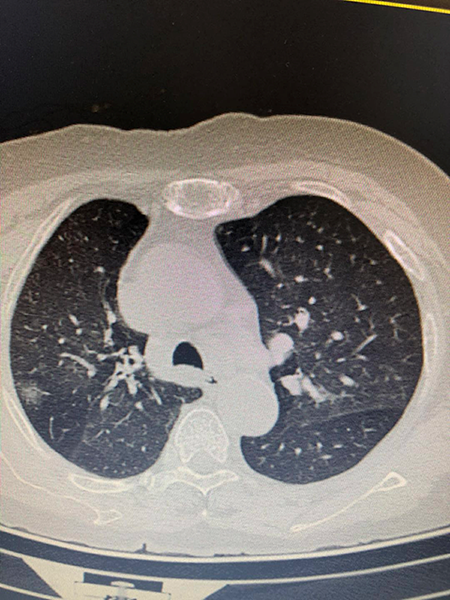

故事二、肺部磨玻璃结节别纠结

徐先生(化名)被查出肺部磨玻璃结节已有数月,且有三个——最大的约7mm,最小的5mm左右。自此,他陷入了惶惶不安,四处寻医,遍查医典,掌握了十分丰富的与肺部结节相关的医学知识。但他还是无法作出决定——开刀,或不开刀?

后经过王剑飞的一番分析与开导,徐先生终于决定手术,术后诊断——最大的是微浸润癌,其余2个是原位癌。虽然从预后看,开刀早晚差别不大,但徐先生终于安心了,又能轻松面对生活了。而对于王剑飞能想病人所想,细心考虑每一个患者的顾虑,徐先生感到十分暖心及感激。